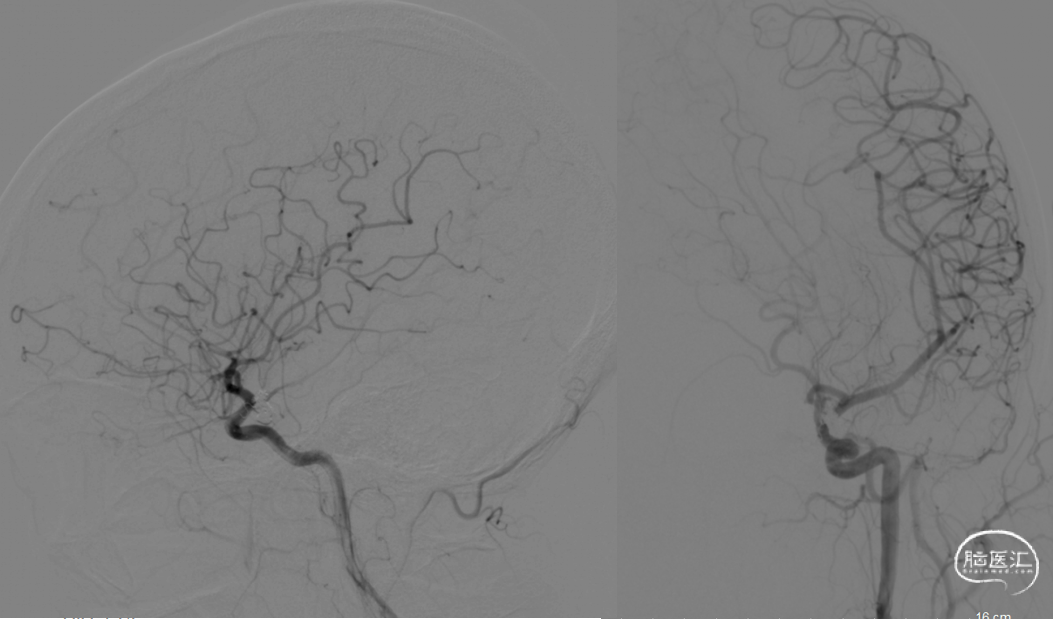

左侧颈总动脉正侧位造影

右侧颈内动脉正侧位造影

复查造影动脉瘤少量充盈,继续将3枚1mm*3cm弹簧圈(EV3)沿子瘤的Echelon-10微导管送入。复查造影示左侧颈内动脉、左大脑中动脉、大脑前动脉、左侧后交通动脉显影良好,动脉瘤栓塞完全。